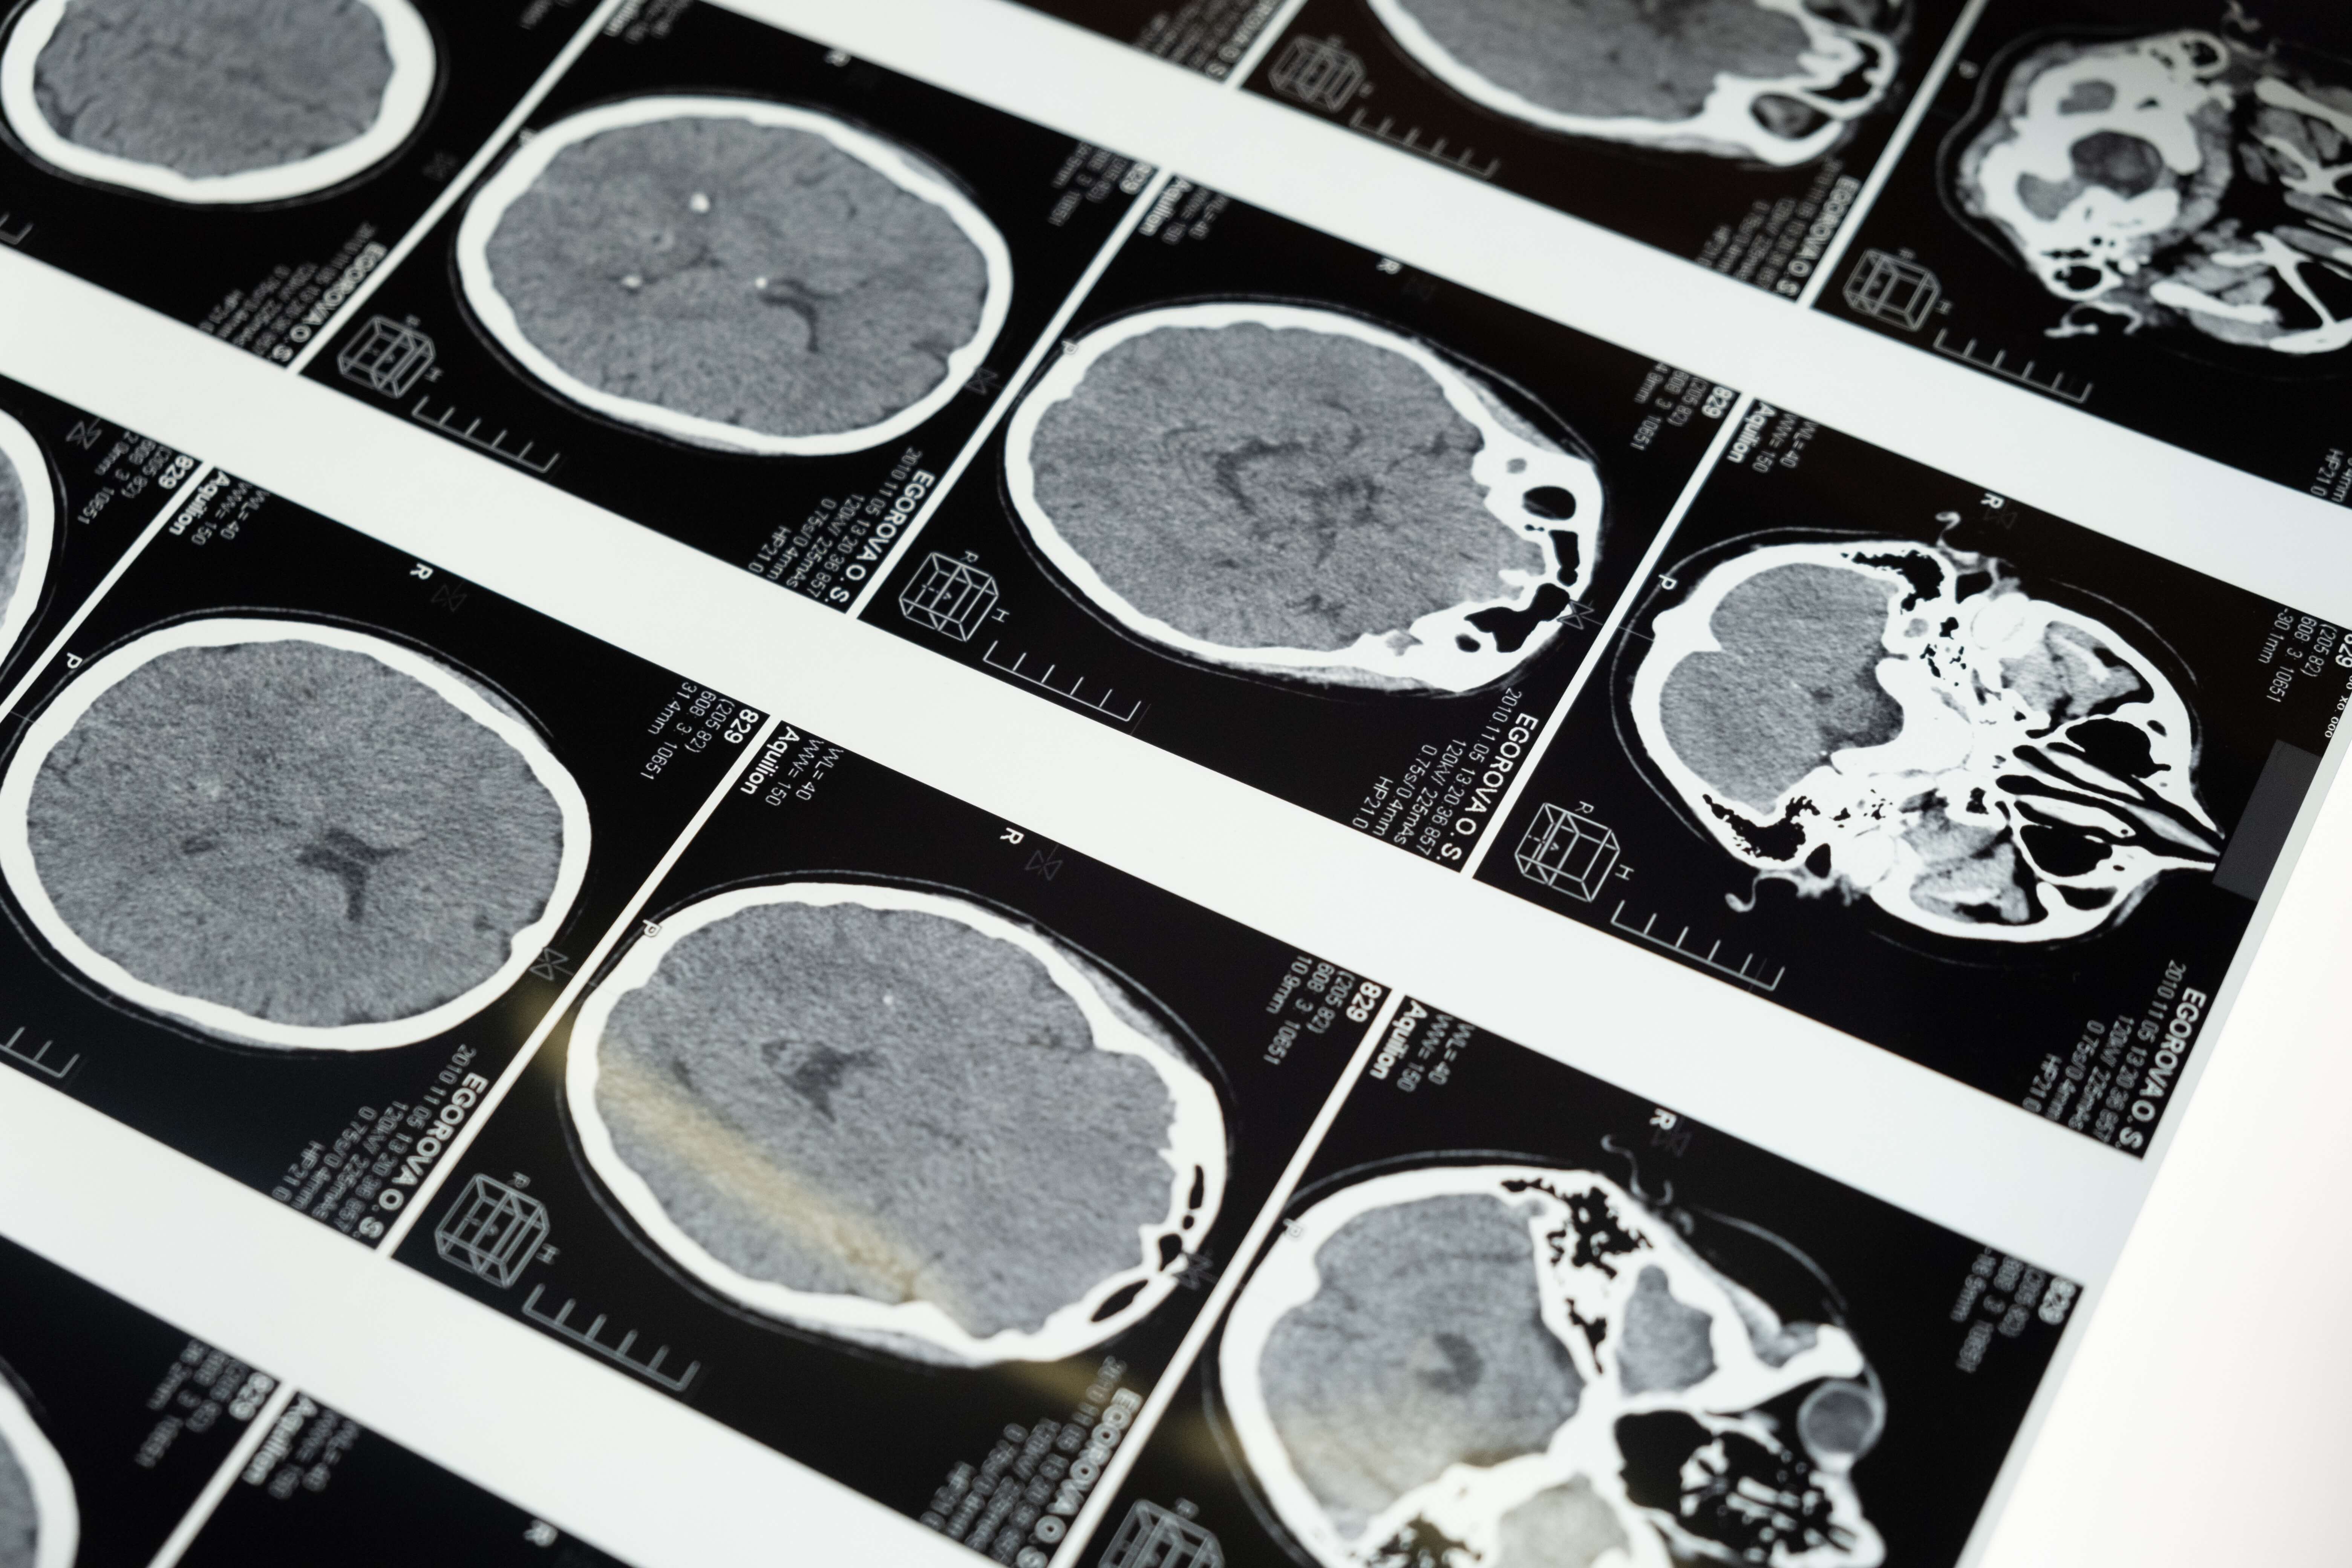

Brain injuries are serious types of trauma that can often lead to long-term hospitalization and care, resulting in high medical costs. Many times, the accidents that lead to a traumatic brain injury are the result of negligence for a variety of reasons. The one thing they have in common besides the trauma is that when it wasn’t your fault, a Pacheco brain injury lawyer can help you or your family obtain the compensation you require to cover those medical expenses and lost wages and pain and suffering.

Traumatic Brain Injuries: How Common Are They?A high number of traumatic brain injuries occur each year. In the United States, 166 people died after sustaining a traumatic brain injury in 2019. More than 233,000 people had to be hospitalized. Even after an initial recovery, TBIs can end up causing emotional, cognitive, physical, behavioral, and social problems.

For example, following a moderate TBI, many people experience some level of recovery following rehabilitation. About half of these patients will show signs of cognitive impairment within the next five-year period or will die. The following severe signs of TBI persist among some survivors after five years, according to the Centers for Disease Control and Prevention:

A TBI happens when someone experiences a jolt or blow to their head that causes a disruption in the way the brain normally functions. The severity of the injury depends on how forceful the trauma was, which is why a TBI can be minor to severe and result in varying periods of unconsciousness or none at all. Medium to severe TBIs or repeated injuries can result in brain damage and memory loss and cause permanent disability. A Pacheco brain injury attorney can help you obtain the compensation you need to care for a loved one who is permanently disabled by a TBI.

Depending on the type and severity of the trauma, brain injuries can range from mild to severe. Hospitalization is not usually necessary for less severe trauma, but it is for more serious ones. How the injury is treated depends on its severity and potential complications:

- Hematoma: Hematomas, caused by ruptured blood vessels, sometimes pool in the brain. In a hematoma, the bleeding occurs on the brain’s surface or between the layers. A hematoma inside the skull can cause swelling and negatively impact brain function. It is often necessary to surgically remove the blood to prevent further damage and death. In older people, hematomas may resorb by themselves if they are small.

- Edema: Swelling in the brain may be caused by an accumulation of fluid. There is no room for the brain to expand within the skull since it is rigidly enclosed. When this happens, the brain cannot get the oxygen it needs. This can lead to irreversible damage or death. Several measures can be taken to reduce the swelling and pressure on the brain.